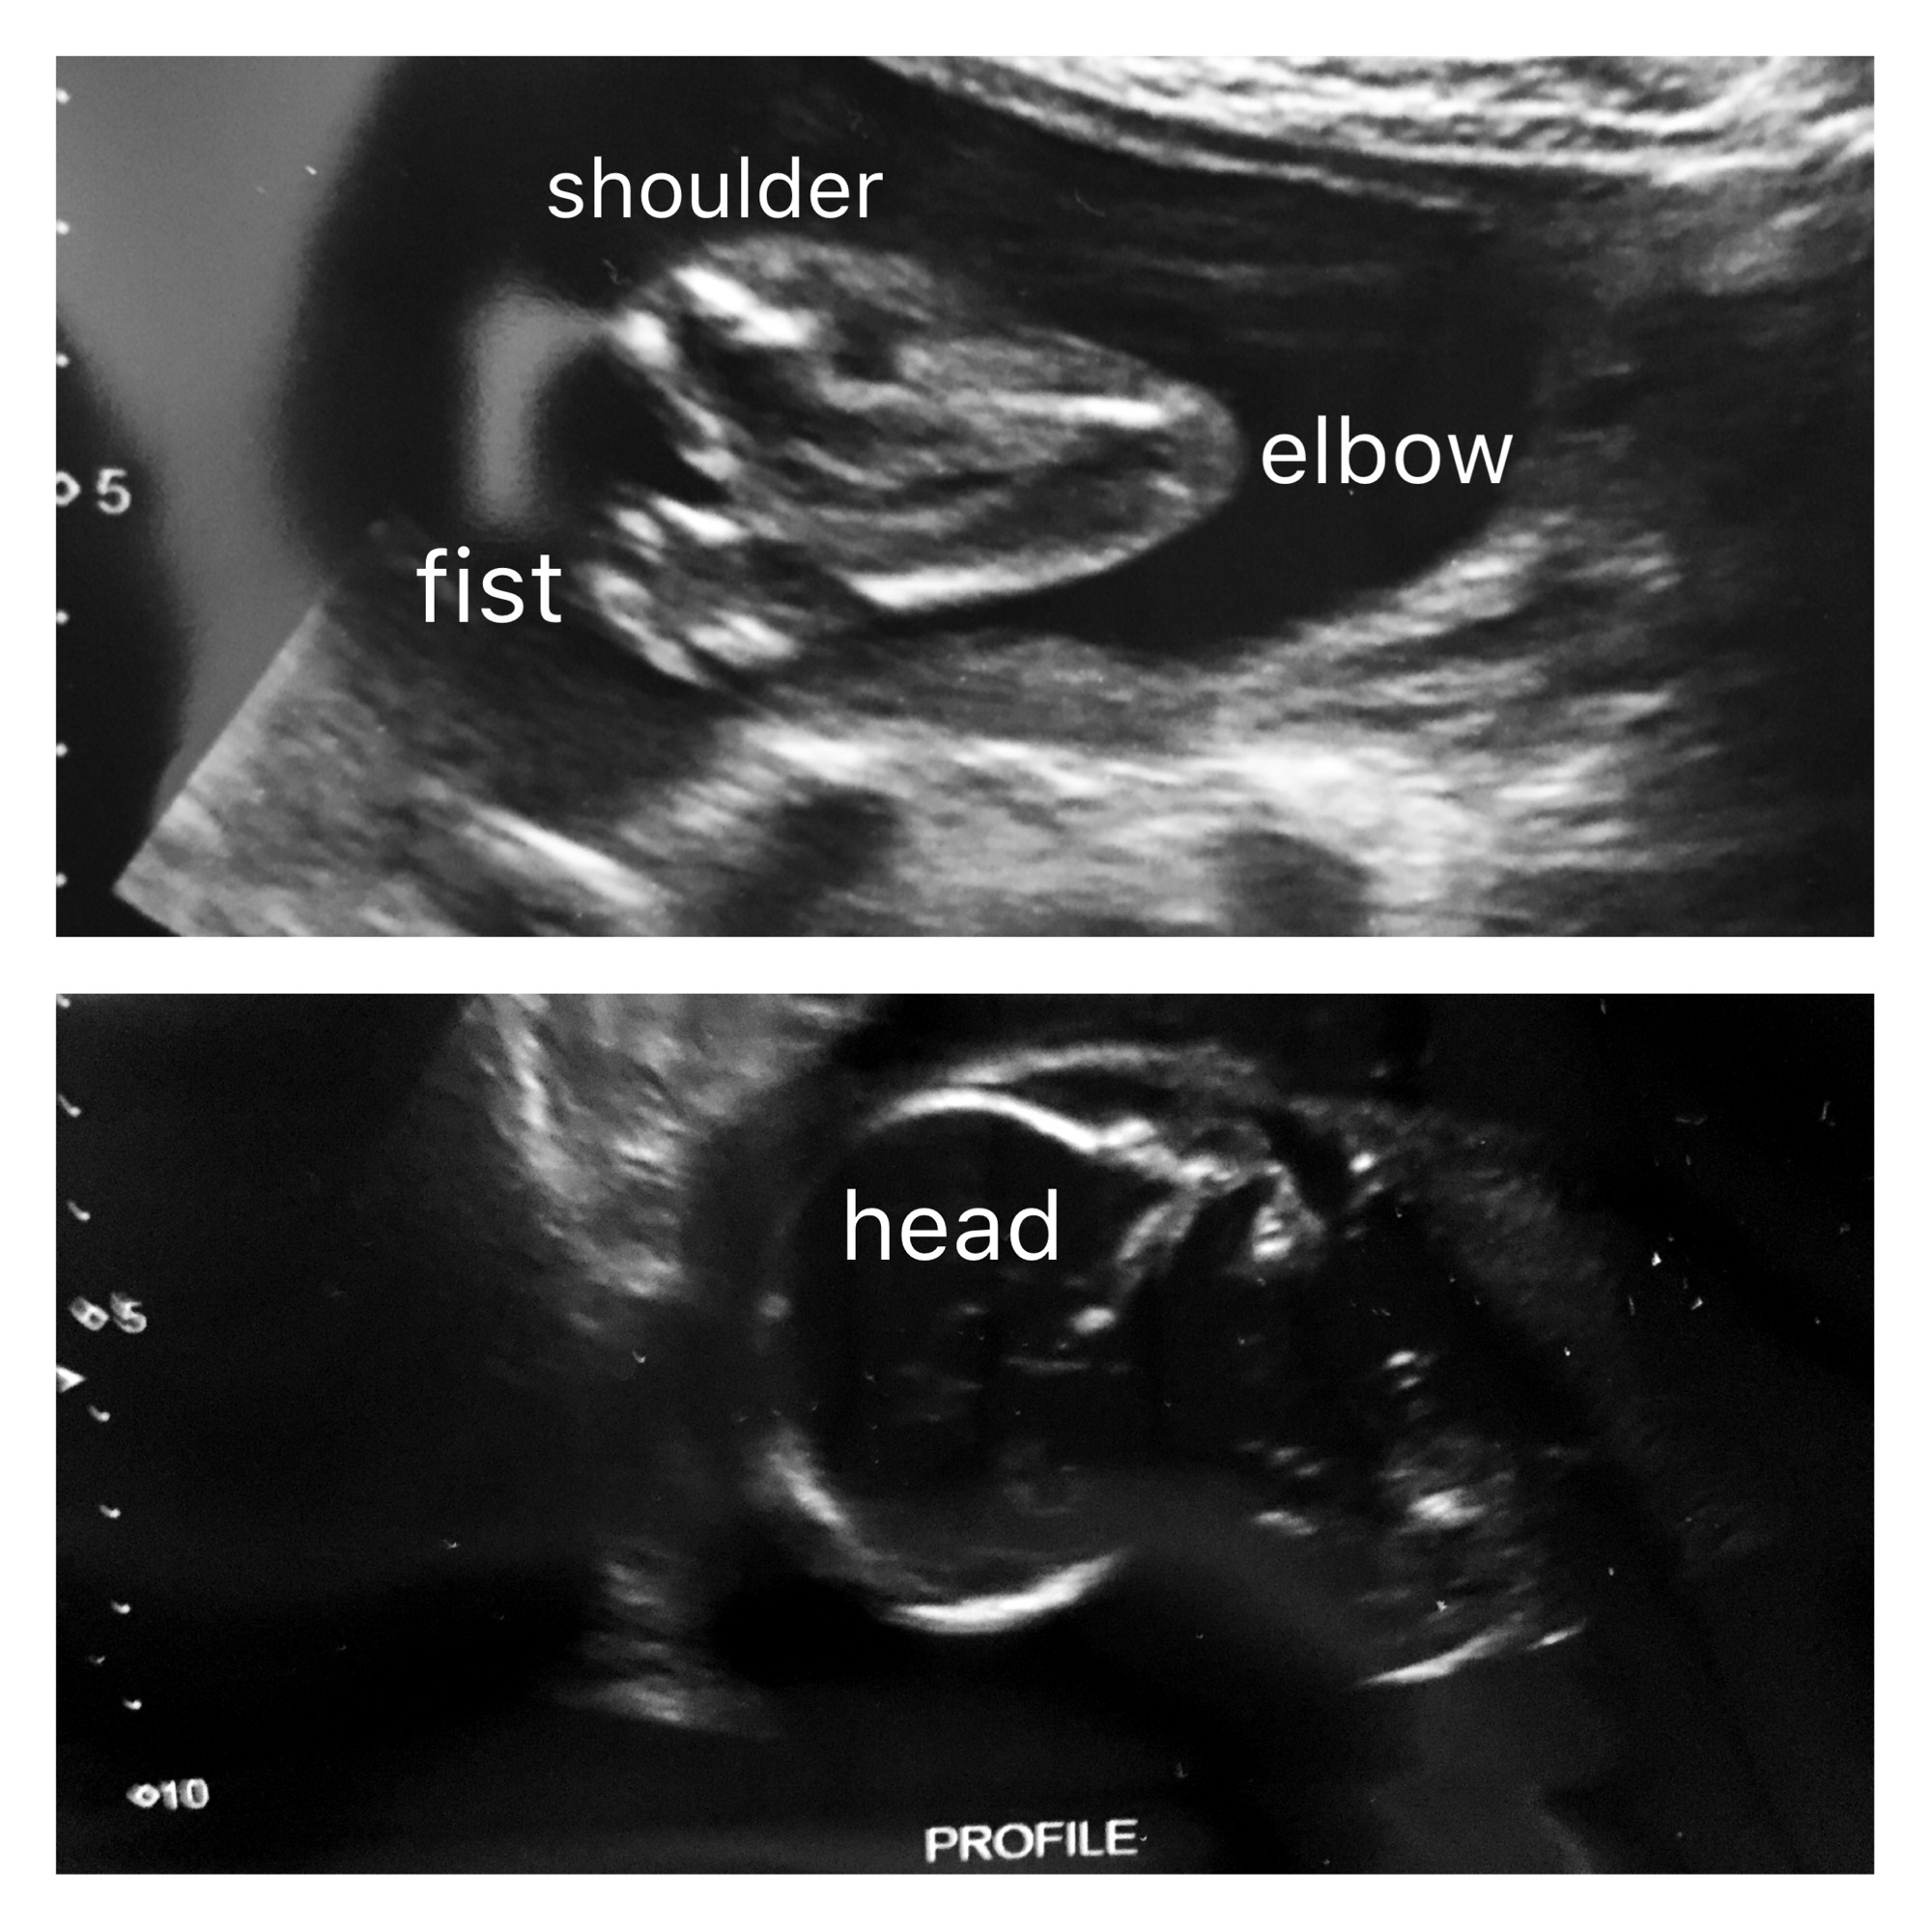

Speaking of Baby, he (that’s right, we’re having a boy!) was very cooperative the whole ultrasound appointment. The technician got a ton of measurements and easily identified baby’s sex. I however, was left a little disappointed  the best ultrasound picture I have of my little guy is his arm. Oh well, I’m sure I’ll more than make up for it with a million pictures when he makes his debut.

Baby Blurry Blob Boy